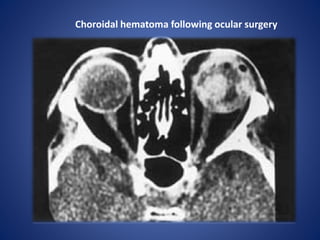

Choroidal hematoma following ocular surgery

• #7 Choroidal hematoma following ocular surgery. Axial CT scan shows multiple choroidal hematomas of various sizes involving the left eye.